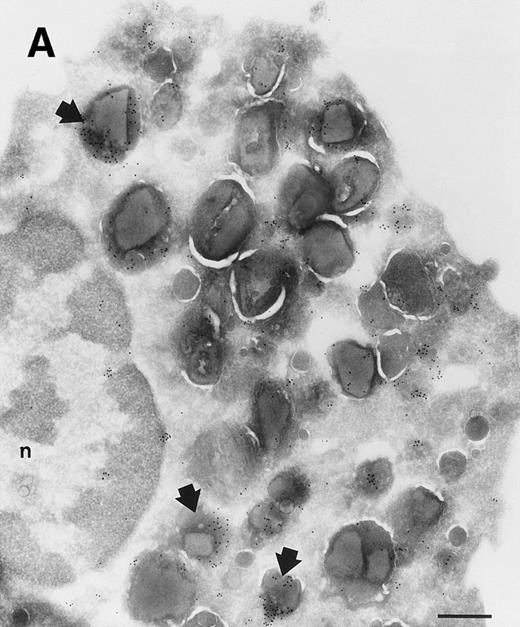

Investigation of the intracellular localization of sPLA2 in unstimulated eosinophils was undertaken by immunoelectron microscopy (immuno-EM). Immunogold-labeled MoAb against sPLA2 was detected in granules that contained the typical eosinophil crystals (Fig 2). It is difficult to ascertain whether the heterogeneity in the labelling in the granules is due to heterogeneity in the localization of sPLA2 or to partial destruction of the epitopes for the antibody due to the fixation procedure used.

Localization of sPLA2 in human eosinophils isolated from peripheral blood. Ultrathin cryosections were incubated with MoAb 10B2, rabbit antimouse IgG and goat antirabbit IgG conjugated to 10-nm gold particles. (A) Overview of an eosinophil showing labeling mainly on the matrix of specific granules, although these granules do show heterogeneity. Nucleus (n); bar = 500 nm. (B) Detail of the cytoplasm showing dense labeling in some granules (closed arrows) and absence of label in others (open arrows). Bar = 200 nm.